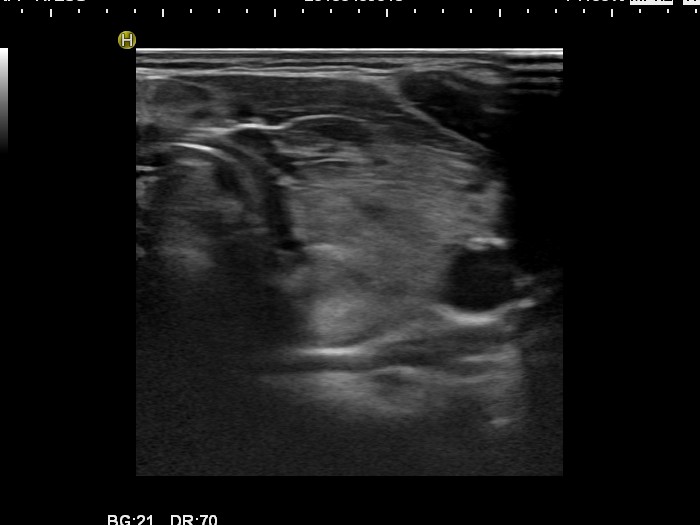

Follow-up investigation 30 months after first visit (ultrasonographic picture 4)

Patient one year after discontinuation of thyrostatics in hyperthyroid state

Left lobe, longitudinal scan. The echogenicity index is around 15%.